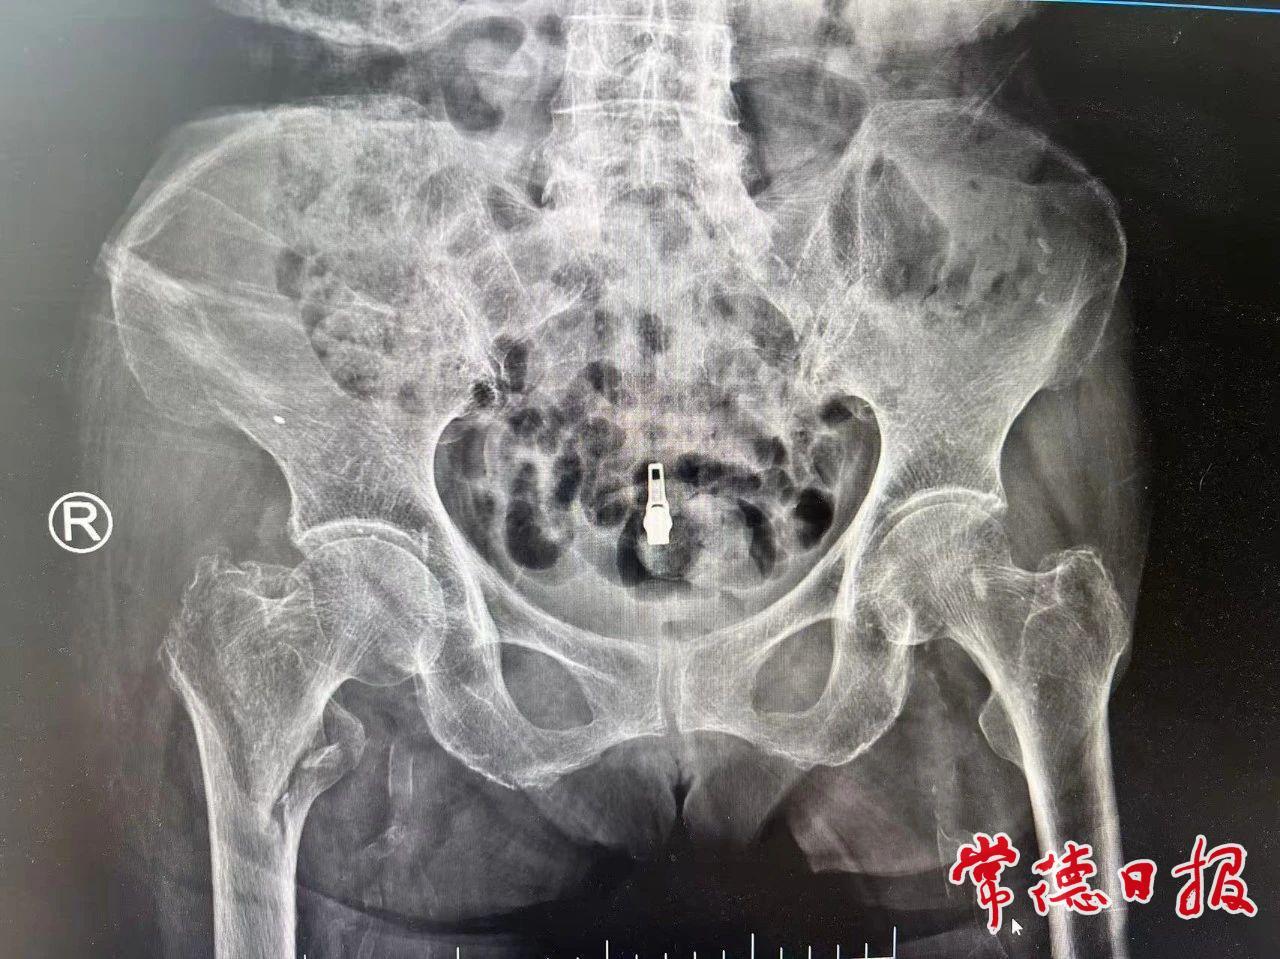

房奶奶患有骨质疏松症,合并糖尿病、心房颤动等基础性疾病,经诊断为右侧股骨转子间骨折。这类骨折被称为“人生最后一次骨折”,如得不到有效治疗,半年内死亡率高达40%。市第一中医医院骨伤二科(创伤二病区)通过术前多学科评估,次日即为患者实施微创InterTAN髓内钉固定术,仅在皮肤切开3个小孔,通过影像引导精准复位骨折并置入髓内钉。术后第一天患者即可完全坐立进食,半个月后康复出院,术后1月左右便能行走活动。